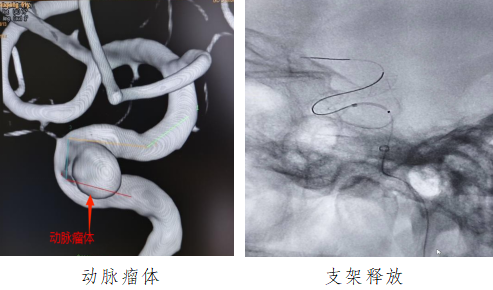

61歲的梁阿姨表情疲倦,因頭暈數(shù)十天來到我院就診,經(jīng)腦血管造影發(fā)現(xiàn)梁阿姨右側(cè)頸內(nèi)動(dòng)脈囊狀動(dòng)脈瘤位于頸內(nèi)動(dòng)脈虹吸彎處,瘤體直徑6毫米,瘤頸寬5毫米,形態(tài)不規(guī)則,此類定時(shí)炸彈如果不積極治療,動(dòng)脈瘤隨時(shí)可能會(huì)破裂,導(dǎo)致蛛網(wǎng)膜下腔出血,可瞬間危及患者生命。

面對(duì)這種特殊情況,我院神經(jīng)介入團(tuán)隊(duì)倪福文主任,朱紅星副主任,陳水洪副主任醫(yī)師等在南方醫(yī)科大學(xué)珠江醫(yī)院神經(jīng)外科中心-腦血管病外科副主任李西鋒教授的帶領(lǐng)下,在麻醉科與介入科通力配合、縝密操作,最終決定打破傳統(tǒng),為梁阿姨實(shí)施“Nuva血流導(dǎo)向密網(wǎng)支架治療顱內(nèi)動(dòng)脈瘤手術(shù),支架貼壁良好,前向血流順暢,載瘤動(dòng)脈血流滯留明顯,不日之內(nèi)完全閉塞。術(shù)后梁姨生命體征平穩(wěn),未出現(xiàn)頭痛、嘔吐及其他神經(jīng)系統(tǒng)癥狀,目前已康復(fù)出院。

神經(jīng)內(nèi)科介入組組長倪福文主任表示:顱內(nèi)動(dòng)脈瘤是發(fā)生在顱內(nèi)動(dòng)脈管壁上的異常膨出,是造成蛛網(wǎng)膜下腔出血的首位病因。顱內(nèi)動(dòng)脈瘤一旦破裂,死亡率可達(dá)30%-50%,幸存患者中仍有高致殘率,且破裂難以準(zhǔn)確預(yù)測(cè),因此稱之為“腦部定時(shí)炸彈”。血流導(dǎo)向裝置可以重建血管內(nèi)血流方向,使動(dòng)脈瘤血栓化,血管內(nèi)皮的再生及修復(fù),最終使瘤頸閉合而治愈。血流導(dǎo)向裝置作為顱內(nèi)動(dòng)脈瘤血管內(nèi)治療的重大突破,體現(xiàn)了傳統(tǒng)治療理念上的轉(zhuǎn)變,為復(fù)雜顱內(nèi)動(dòng)脈瘤的治療帶來了全新方法。